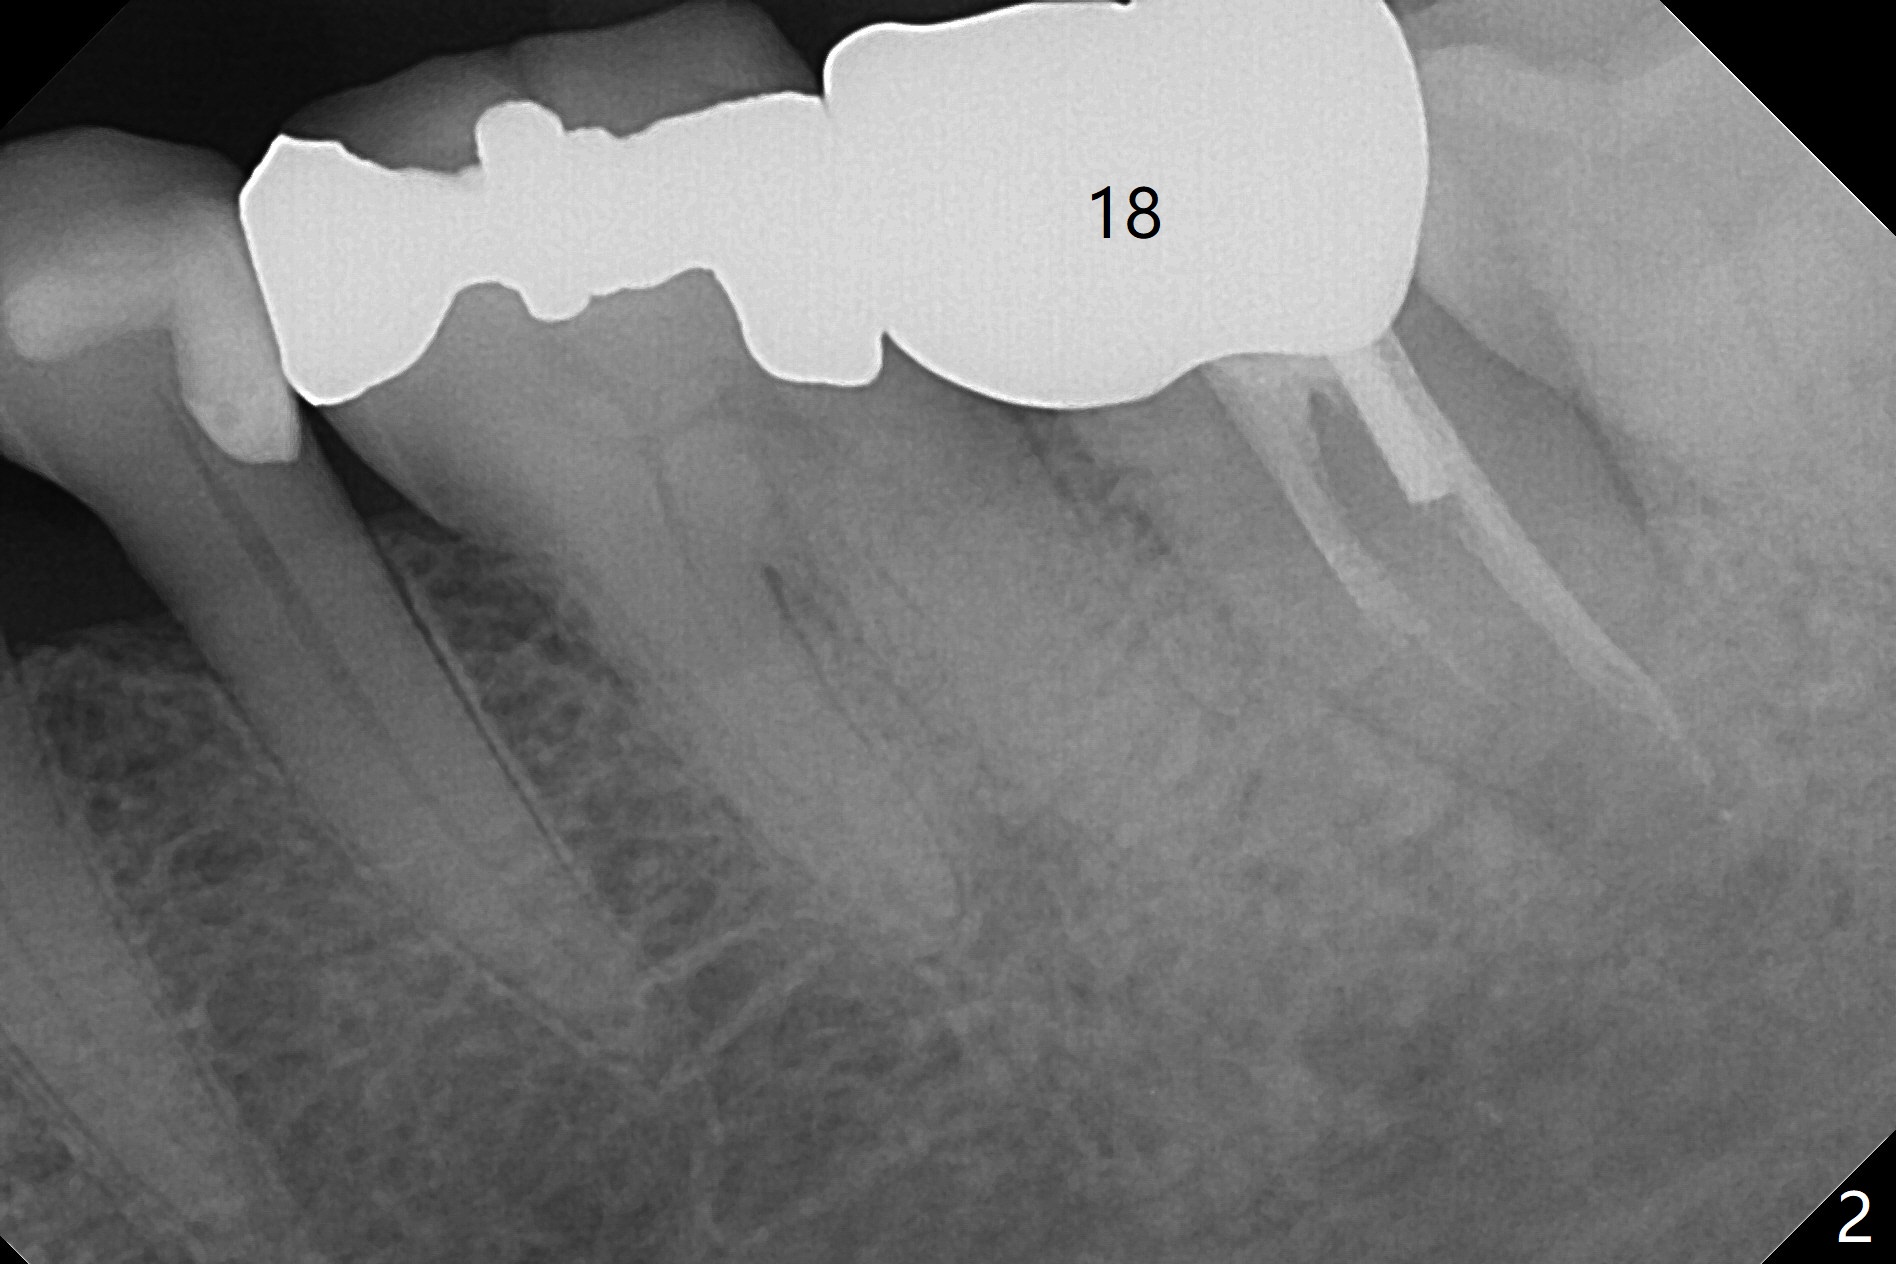

A 76-year-old man initially (3 years ago) presented to clinic for implant consultation 2 weeks after #2 extraction due to root canal failure. A 7x17 mm tissue-level implant was placed following bone expansion and tapping ~ 4 weeks post extraction. A 6x3 mm unipost was placed for immediate provi-sional. Impression was taken with retightening the unipost (no cementation) 3 months postop. Two weeks post cementation, the patient started to report food impaction at #18 crown (Fig.1). Eight months later, distal open margin was found; the tooth #3 seems to have occlusal trauma. Ten months later, #2 and 3 contact remains normal. Finally the crown at #18 was redone. ~1.5 years post cementation, #2 crown proximal contact becomes loose. The crown was redone with no occlusal contact. Retrospectively it is due to mesial shifting of the tooth #3. Nine months post cementation, the tooth #18 shows sign and symptom of root fracture (Fig.2). Antibiotic appears to alleviate the pain. Occlusal adjustment is done at #30 pontic to reduce trauma to #3 with symptom improvement (Fig.3).